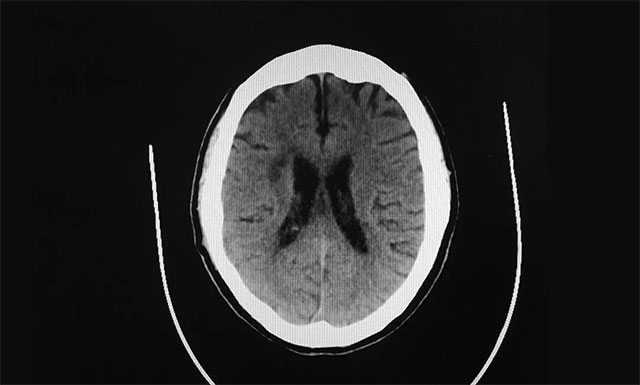

▲ 患者多发性脑梗,致使双下肢活动障碍

“在该医院老伴进行了头部CT检查,医生告诉我们他为多发性脑梗,听到‘脑梗’两字,当时心里咯噔了一下,因为身边有许多老人突发脑梗,之后大多都长期偏瘫在床,恢复好得很少,加之老伴还身患多种疾病,真怕他以后只能在轮椅和床上度过了”,每想到这里,妻子管女士有些不知所措。